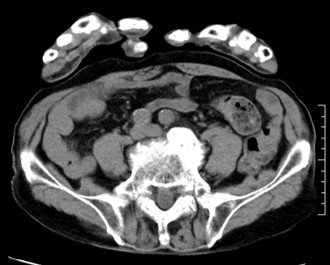

ハイピッチ使用時でも、画像を比較すると読影可能な画質を維持できている。図6の写真は左内腸骨動脈瘤の病変である。左側は患者が3か月に1回行っている定期フォロー時に撮影した通常ピッチ(0.984:1)の画像、右側は救急搬送時に撮影したハイピッチ(1.357:1)の画像であるが読影に影響が出る程の画質の差は感じられない。

Maxima_hachiojisanno10.jpg

図6 ピッチの違いによる左内腸骨動脈瘤の見え方の違い